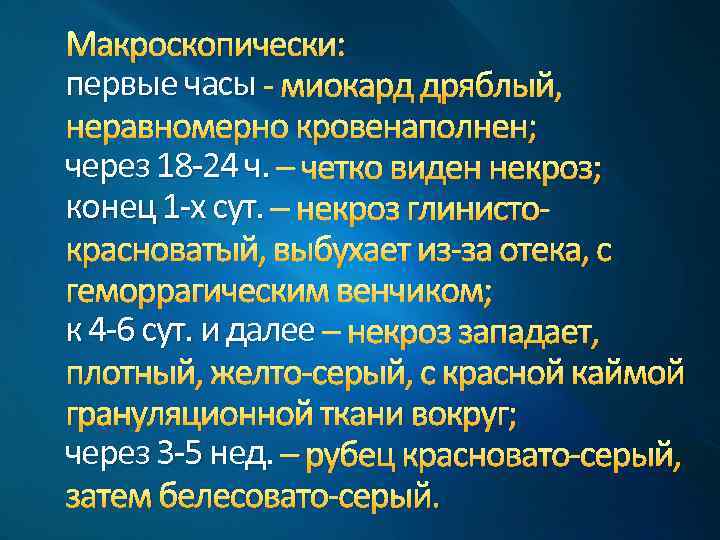

Макроскопически: первые часы - миокард дряблый, неравномерно кровенаполнен; через 18 -24 ч. – четко виден некроз; конец 1 -х сут. – некроз глинистокрасноватый, выбухает из-за отека, с геморрагическим венчиком; к 4 -6 сут. и далее – некроз западает, плотный, желто-серый, с красной каймой грануляционной ткани вокруг; через 3 -5 нед. – рубец красновато-серый, затем белесовато-серый.